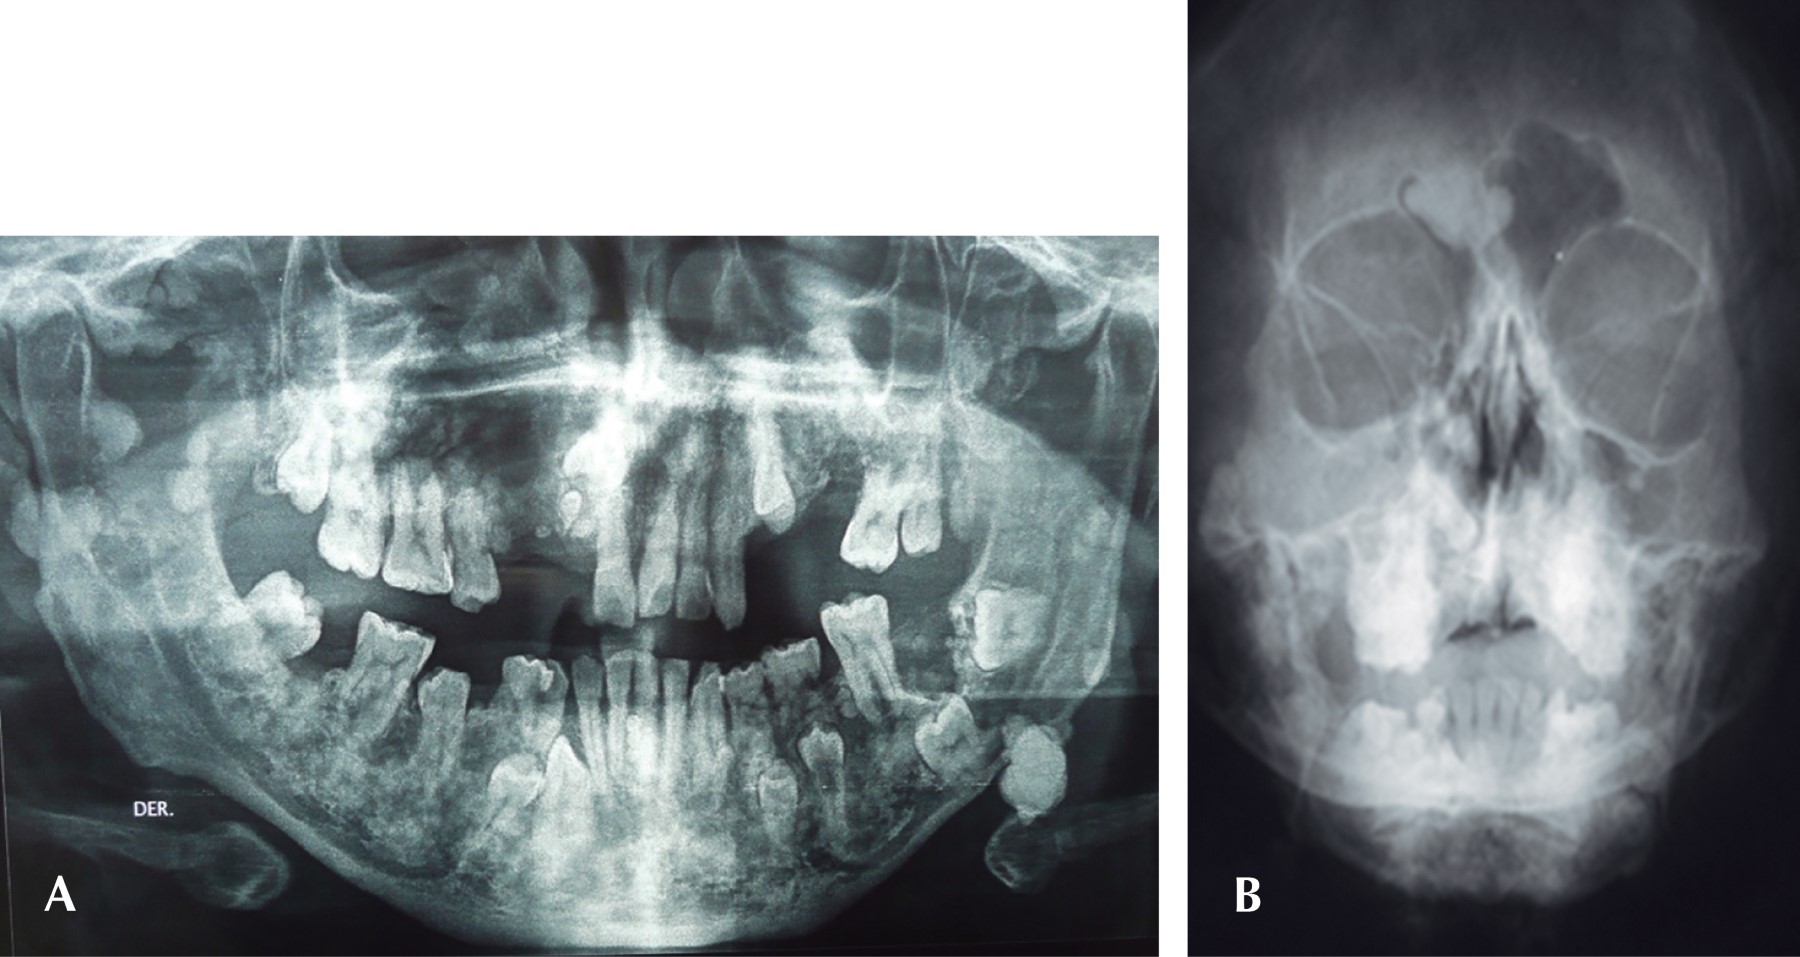

Se trata de un hombre de 42 años que acude a consulta para valoración dental. A la exploración clínica se encontraron hallazgos que se apartaban de la normalidad como áreas induradas en cráneo y cara, a pesar de que el paciente no presentaba ningún aumento de volumen visible notorio, por tal motivo, se le solicitó una radiografía panorámica donde se aprecian hallazgos atípicos como la presencia de algunos dientes primarios, retenciones dentarias, dientes supernumerarios, múltiples zonas con aumento de la densidad ósea tanto en maxilar como en mandíbula (Figura 2).

Dadas las características que presentaba, se le solicitó una proyección de Waters donde se aprecia el seno frontal derecho ocupado por una masa sólida.

Dadas las manifestaciones descritas con anterioridad a nivel maxilomandibular, el síndrome de Gardner presenta alteraciones dentales específicas hasta en 75% de los casos, dentro de las cuales destacan la agenesia dental, múltiples dientes ectópicos, permanencia de dientes deciduos, hipercementosis, odontomas, quistes dentígeros, retenciones dentarias, dientes supernumerarios y fusiones dentales.2

MANIFESTACIONES DENTALES